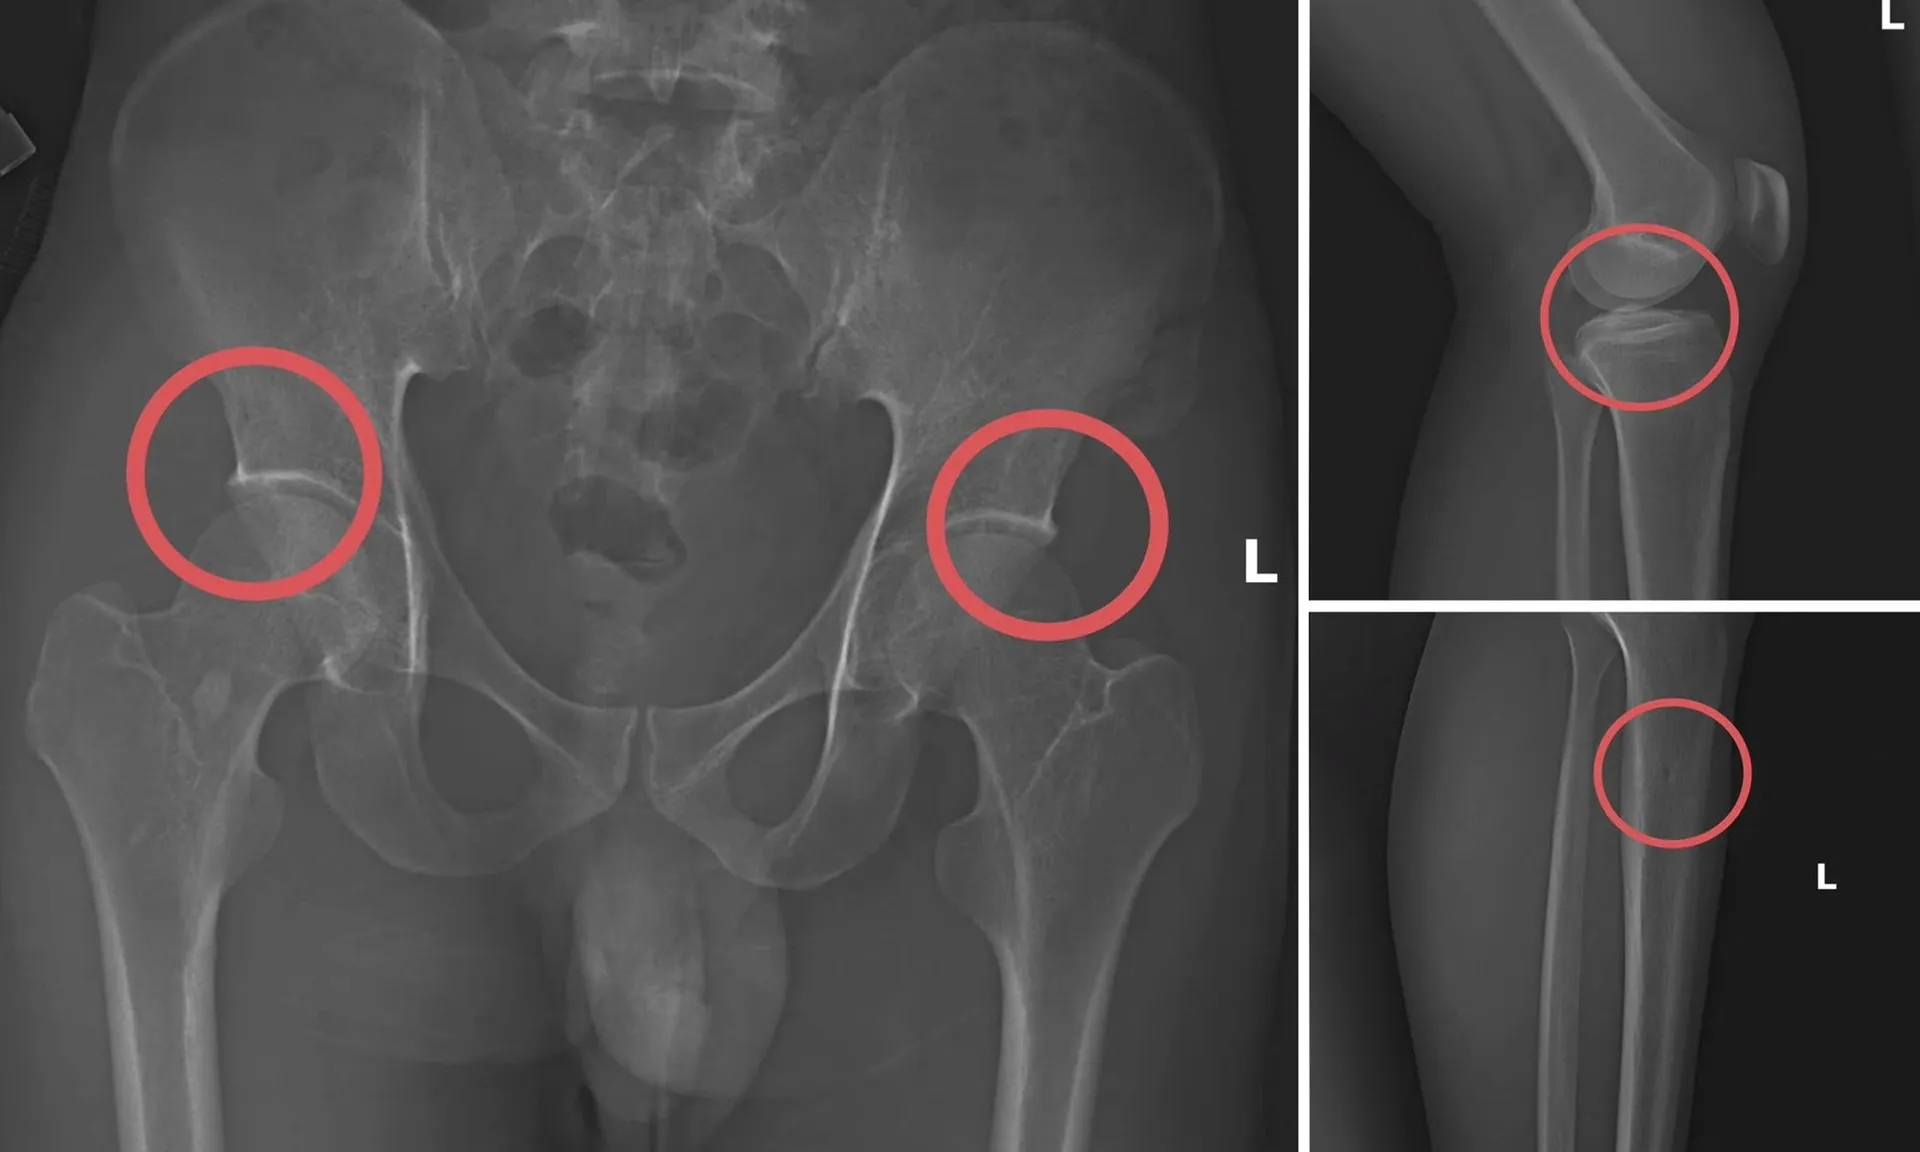

Đáng chú ý, Châu trực tiếp thực hiện hành vi tiêm thuốc mê, rồi dùng kim tiêm, búa, đinh để tác động vào xương người mua bảo hiểm, tạo nên các vết nứt, vỡ xương tương tự tai nạn thật.

Theo Công an tỉnh Phú Thọ, thủ đoạn này vừa tàn nhẫn, vô nhân tính, coi thường sức khỏe, tính mạng của người tham gia, vừa được tính toán kỹ để gây thương tích đúng vị trí có mức chi trả cao, khiến các công ty bảo hiểm khó phát hiện dấu hiệu gian dối.